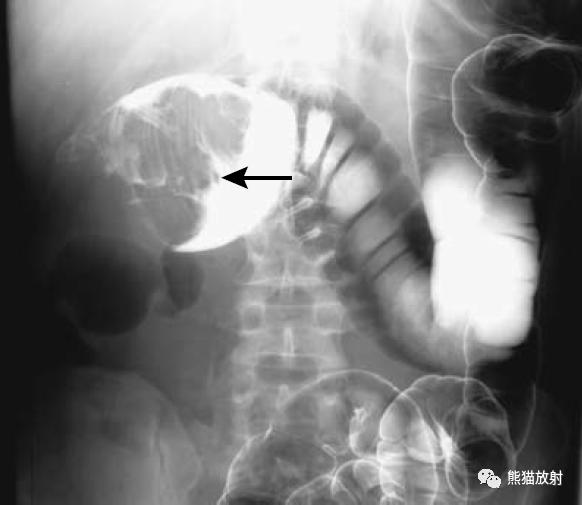

结-结肠肠套叠(箭头)。此例病因很罕见,为结肠子宫内膜异位。

结-结肠肠套叠,由盲肠癌所致。钡灌肠显示横结肠中的肠套叠(箭头),在进一步的压力下,肠套叠移位至升结肠。